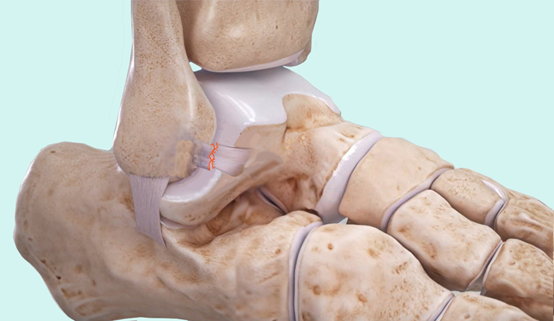

(六)关节镜下韧带加强术:Internal Brace

▶Internal Brace:该技术通过在距腓前韧带的起点和止点位置植入生物复合材料钉和纤维绳来增强韧带的稳定性。

▶可用于治疗韧带急性损伤和慢性踝关节不稳。

图6:距腓前韧带撕裂(急性损伤)